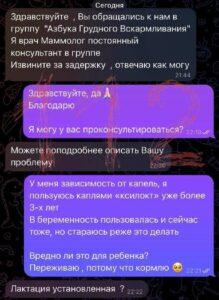

В чате молодых мам появился мошенник, выдававший себя за врача-маммолога и требовавший интимные фото для «диагностики». Подписывайтесь...